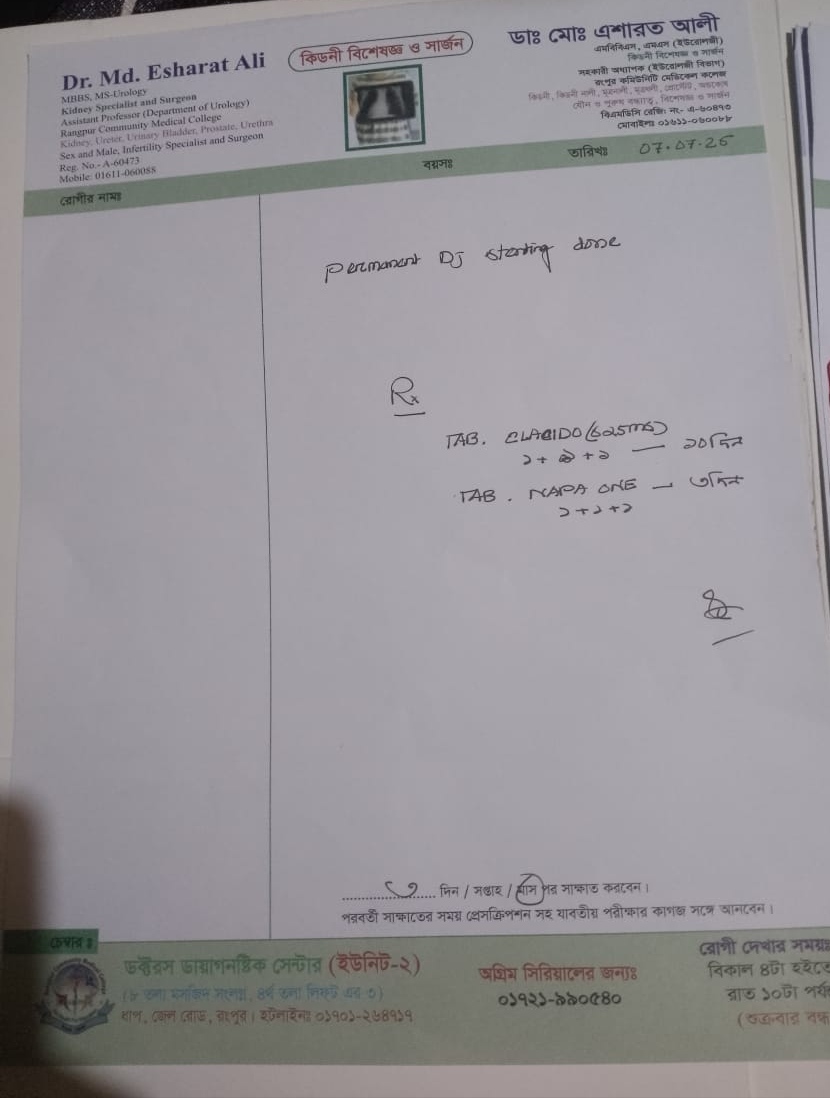

#250909I: জটিল কিডনি সমস্যায় আক্রান্ত শহিদুল ইসলাম চিকিৎসার জন্য সাহায্য চেয়েছেন, গ্রাম: মহব্বতপুর, জেলা: দিনাজপুর।